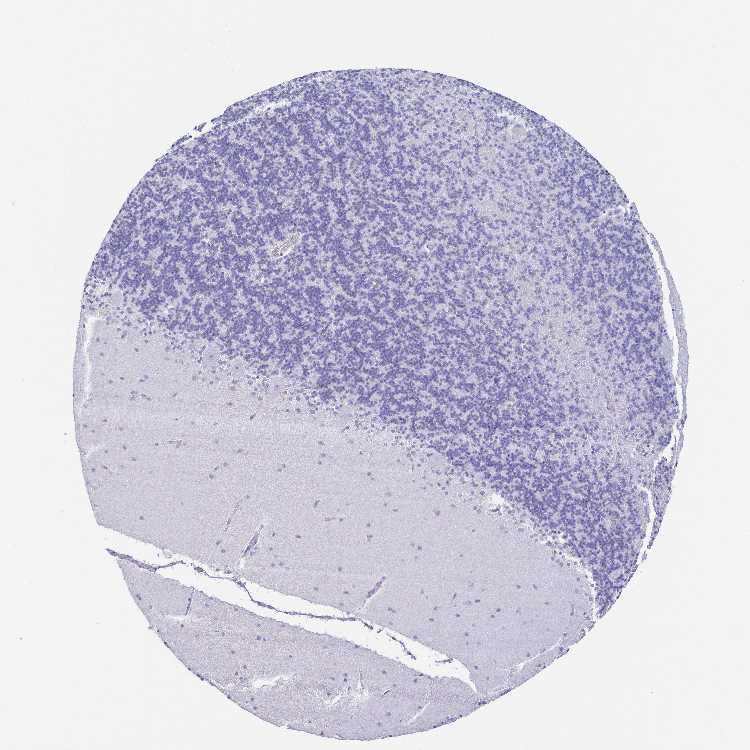

CEREBELLUM - Antibody stainingi

Antibody staining in the annotated cell types in the current human tissue is reported as not detected, low, medium, or high, based on conventional immunohistochemistry profiling in selected tissues. This score is based on the combination of the staining intensity and fraction of stained cells.

Each image is clickable and will lead to virtual microscopy that enables deeper exploration of all samples and also displays staining intensity scores, fraction scores and subcellular localization as well as patient and tissue information for each sample.

Antibody HPA047684

Purkinje cells Not detected

Cells in granular layer Not detected

Cells in molecular layer Not detected